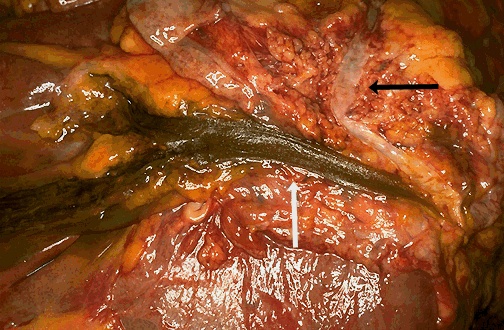

| The common bile duct appears above the white arrow, and branches into the cystic duct (lower) and hepatic duct (higher) at the left. The black arrow appears to the right of the pancreatic duct. Both the pancreatic duct and the common bile duct merge at the ampulla at the lower right. This anatomic configuration, present in most persons, makes pancreatitis from gallstones impacting in the ampulla of Vater possible. |